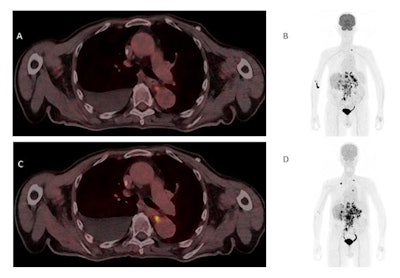

(A) Single-tracer PET/CT with F-18 FDG showing fused images in the axial plane of a primary tumor at the gastroesophageal junction with a metastasis in the left adrenal gland and liver metastases. (B) Maximum intensity projection (MIP) of single-tracer PET images displaying high uptake in brain tissue, tracer accumulation around the injection side at the right elbow, lymph node metastasis in the left upper mediastinum, multiple abdominal lymph node metastases, and liver metastases. An additional benign accumulation of FDG is visible, caused by right-sided thoracolumbar osteoarthritis. (C) Transverse section of fused dual-tracer F-18 FDG and Ga-68 FAPI-46 PET/CT of the same patient. (D) As all images were visually normalized to the uptake of the liver, MIP of dual-tracer PET/CT in the same patient shows a less pronounced tracer accumulation in the brain tissue, compared to single-tracer PET/CT. In addition to lesions detected with single-tracer PET/CT, further abdominal lymph node metastasis and liver metastases are visualized via dual-tracer PET/CT. The focal tracer accumulation in the right vein angle is due to intravenous tracer accumulation from the former tracer depot at the right elbow. Image courtesy of the Journal of Nuclear Medicine.Since the diagnostic performance of Ga-68 FAPI-46-PET/CT is best shortly after injection and F-18 FDG-PET/CT is currently the gold standard, the authors so far recommend the injection of Ga-68 FAPI-46 as a second tracer after the F-18 FDG-PET/CT scan.